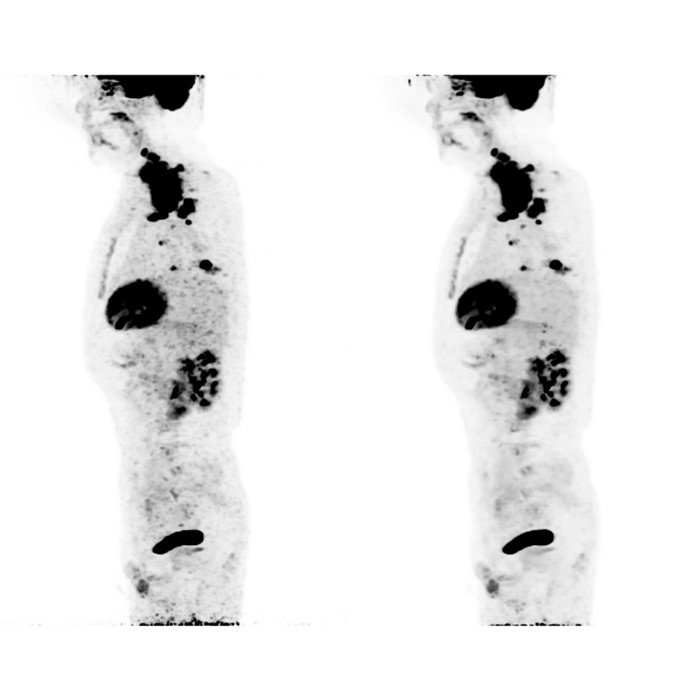

▲左:50%低劑量圖像,右:新型AI重建圖像

上圖中,新型AI重建圖像的噪聲水平大大低于傳統(tǒng)低劑量重建結(jié)果(約為原來的50%),圖像信噪比顯著提升。